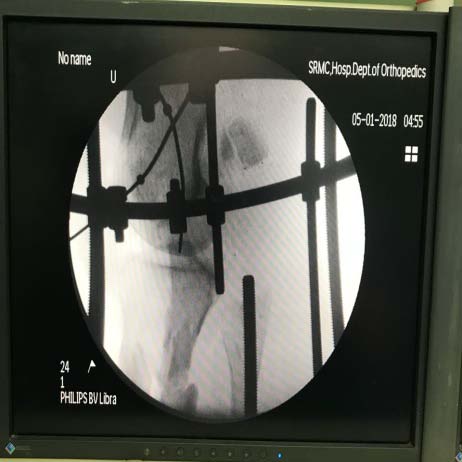

27 Year old gentleman who sustained an open grade 3c Gustilo-Anderson fracture with right floating knee that was initially treated with debridement and external fixator and advised amputation above knee in outside hospital and presented to us within 12 hours of initial injury. On head to toe examination, no other musculoskeletal and organ injuries were present. On initial presentation, he was hypotensive (blood pressure-90/70 mm of hg) and was started on appropriate measures by emergency room team. No known medical co-morbidities were present. He was non smoker, non alcoholic and no drug addiction. On local examination of right lowerlimb: a. Right lower limb knee spanning external fixator present. b. Lacerated wound of size 20x10 cm extending from distal third of thigh to middle third of leg anteriorly. Wound contamination present (fig. 1). c. Both femoral condyle fractured fragments and proximal tibial fractured fragments exposed (fig. 1). d. Patella and lateral tibal condyle absent (fig. 1). e. Tendons and muscles were exposed (fig. 1). f. Dorsalis pedis artery pulsation-feeble. g. Posterior tibial artery pulsation-absent. h. Sensations over right lower limb were intact. -2) was used to assist in the decision of injuries that also had a vascular component and the total score was found to be 7 (? 7 should be consider for amputation). In view of partial vascular injury (Anterior tibial artery pulsation feeble and Posterior tibial artery pulsation were not felt), Ganga Hospital Open Injury Severity Score (GHOISS) was also used which was found to be in borderline range of 16 score (Table -1). Scoring systems provided limited diagnostic benefit. Thus, we had an extensive discussion with the patient and his relatives, in order to point out that any attempt at limb salvage might result to major complications and probably a delayed amputation. In addition, even with salvage severe disability was expected. After discussing and taking consent from patient and his relative he was taken up for combined procedure under orthopaedic and plastic surgery team after obtaining anaesthetic fitness. He underwent right leg and knee wound debridement and reconstruction with ilizarov fixator and soft tissue repair. Intraoperatively, Patella and lateral tibal condyle was found to be absent (fig. 1,5,6). Patella tendon was sutured to quadriceps tendon. Postoperatively, he was shifted to intensive care unit in view of raised serum myoglobin and CPK levels for which cardiology opinion were sought. After 1 week, patient underwent right leg ilizarov realignment and wound debridement with medial gastronemius flap + split skin grafting + vacuum assisted closure (fig. 17). Introperative period was uneventful. Intraoperatively gram, fungal and acid fast bacilli stain and culture was sent and found to be negative for organism growth. Postoperatively regular wound inspection and dressing done which was found to be satisfactory clean (fig. 17, 18). Blood culture and urine culture shows no growth. He was afebrile (initially he was hypotension which was controlled during the course of treatment) and was hemodynamically stable. Gustillo and Anderson´s classification (fig. 4) was used in order to highlight the contamination and the soft tissue injuries as a risk factor in the fracture evolution. It was classified as grade 3c (as vascular injury was present). He was started on rehabilitative care. Range of motion of knee was found to be 0 to 40 degree of flexion with some instability (fig. 18). Strict non weight bearing walking with walker support was encouraged. Quadriceps and hamstring muscle strengthening exercise was started. The treatment was deemed successful and the patient was discharged. Regular xray radiography was taken to assess fracture union (fig. 2, 3, 7, 8-16). Fracture union for distal femur was seen at 8 months and for tibia it was 12 months. He was followed up for the period of two years and he is doing symptomatically better.

There are many studies in literature suggesting internal fixation of both the fractures of floating knee should be done as early as possible [35]. Ratliff found that internal fixation of both fractures was less likely to cause the development of knee stiffness and lessen the duration of hospital stay [36]. Ostrum treated patients with retrograde femoral nailing and antegrade tibia nailing through 4 cm medial parapatellar incision [37]. The average time to union of femoral fracture was 14.7 weeks and for tibial fracture was 23 weeks. Theodoratos et al. [21] recommended intramedullary nailing as the best choice of treatment, except for grades IIIB and IIIC open fractures. In our case report, patient was treated with initially by application of external fixator followed by ilizarov fixator application. Time to union of femoral fracture was 8 months and for tibia fracture was 12 months.

With great effort and good team work (like vascular and orthopaedic surgeons) badly comminuted compound injuries (Type III C injury) can be managed well with Ilizarov fixation. Even though the decision of amputation versus Salvage was based on more scientific / scoring system, patient's option should be taken, especially in borderline cases considering the present medico legal scenario.